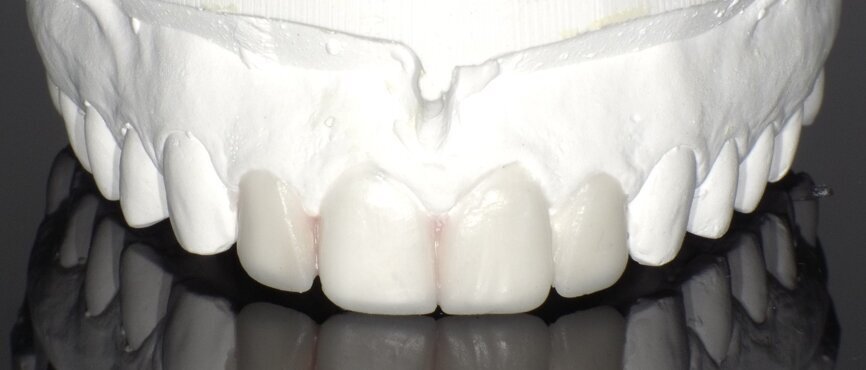

After the treatment planning discussion, the patient requested to proceed with direct resin-bonded composite veneers to enhance her smile. After the old composite fillings were removed (Fig 3, 4), smile design, was done to restore the golden proportion by modifying the shape and size of the teeth. Based on the smile design a mock-up was created to help obtain patient approval on the expected outcome and fabricate the silicone index.

Fig 8 : Silicone Index fabricated with putty impression material

Fig 9 : index with incisal wrap to help duplicating the thickness of the incisal edge

Silicon index

Silicone index with putty impression material was used to create the palatal shell of the restoration for each tooth separately (Fig 8).

Tip: make the index with incisal wrap to help duplicating the thickness of the incisal edge (Fig 9).